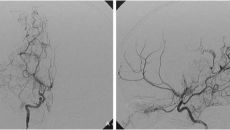

'아지랑이처럼 뇌혈관 피어오르는' 모야모야병, 뇌출혈 발생 원인 밝혀져

경희대병원 연구팀, '후방 모야모야 혈관 파열' 원인 규명 모야모야병은 뇌에 혈액을 공급하는 뇌 속의 특정 혈관(내경 동맥 끝- 2023-09-30 09:42